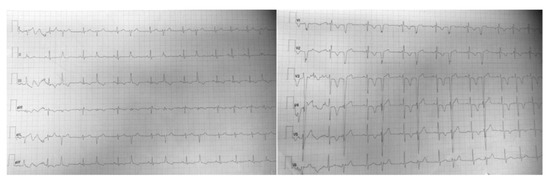

No complications during or after surgery were reported, and the intraoperative transesophageal echocardiography (TEE) showed no residual lesion and RVOT obstruction was totally relieved.

Transesophageal echocardiogram through the mid-esophageal 30° and 60° view, before and after surgery resection of myxoma, shows the complete resolution of RVOT obstruction.